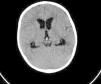

Se presenta el caso de un lactante de 8 meses con traumatismo craneoencefálico tras caída de los brazos de su madre. A las 6 h del traumatismo presenta disminución progresiva del nivel de consciencia (Glasgow 10), hipertonía e hiperextensión de extremidades y ojos en sol poniente, con desviación conjugada de la mirada hacia la izquierda, acudiendo a hospital comarcal. A las 2 h llega a nuestra unidad de cuidados intensivos pediátricos (UCIP), constatándose frecuencia cardiaca de 100 latidos/min y presión arterial normal. Se administró terapia hiperosmolar con suero salino hipertónico, sin apreciarse respuesta. Se realizó una TC craneal, objetivándose sangre a nivel de acueducto de Silvio y el cuarto ventrículo junto a discreta-moderada dilatación triventricular. No se observaron lesiones no traumáticas, ni otras lesiones secundarias al traumatismo (fig. 1). En algo más de media hora desde el ingreso en la UCIP, se colocó derivación externa de LCR y a la vuelta de quirófano había desparecido la clínica de hipertensión intracraneal. La RM y angio-RM cerebrales realizadas a los 9 días evidenciaron la resolución completa de la hidrocefalia y del sangrado, no encontrándose anomalías acompañantes, por lo que se retiró la derivación externa con evolución favorable. El paciente permanece asintomático transcurridos 3 meses del accidente.

Una causa importante de hidrocefalia adquirida es la hidrocefalia posthemorrágica. Habitualmente, la sangre, al alcanzar el espacio subaracnoideo, induce una respuesta inflamatoria seguida de fibrosis, produciendo una disminución en la reabsorción de LCR, con la consiguiente hidrocefalia no obstructiva o comunicante. Mucho menos frecuente es que la hidrocefalia posthemorrágica se produzca por un mecanismo obstructivo, es decir, que se cree una obstrucción al flujo de LCR en algún punto del sistema ventricular. En el caso descrito, un sangrado a nivel del acueducto de Silvio provocó una dilatación proximal del sistema ventricular, observándose una hidrocefalia triventricular, que fue además transitoria puesto que se resolvió espontánea y completamente una vez reabsorbido el sangrado. El deterioro progresivo durante 2 h del estado de consciencia junto a bradicardia moderada y la evidencia de hidrocefalia aguda, en ausencia de midriasis, junto con la resolución del cuadro tras la derivación de LCR, son compatibles con hipertensión intracraneal, siendo muy poco probable un estatus convulsivo.